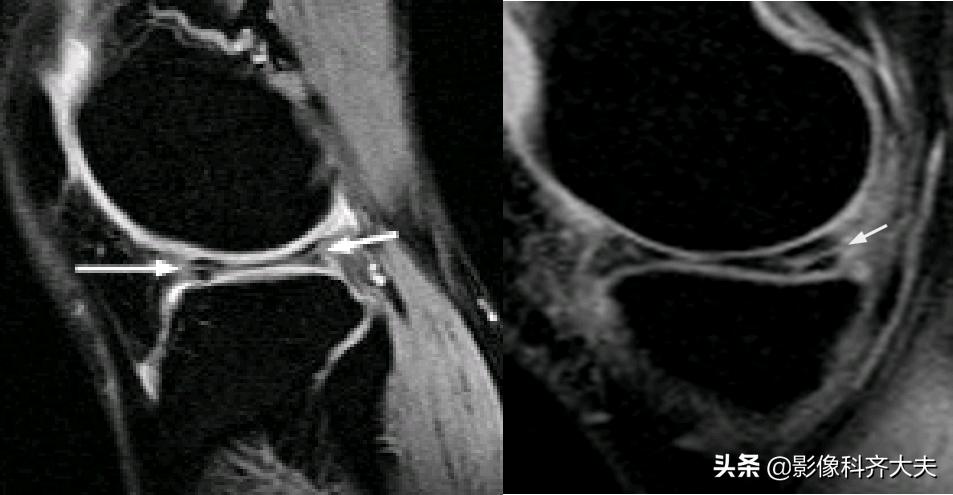

腘肌腱腱鞘:

后股板韧带: